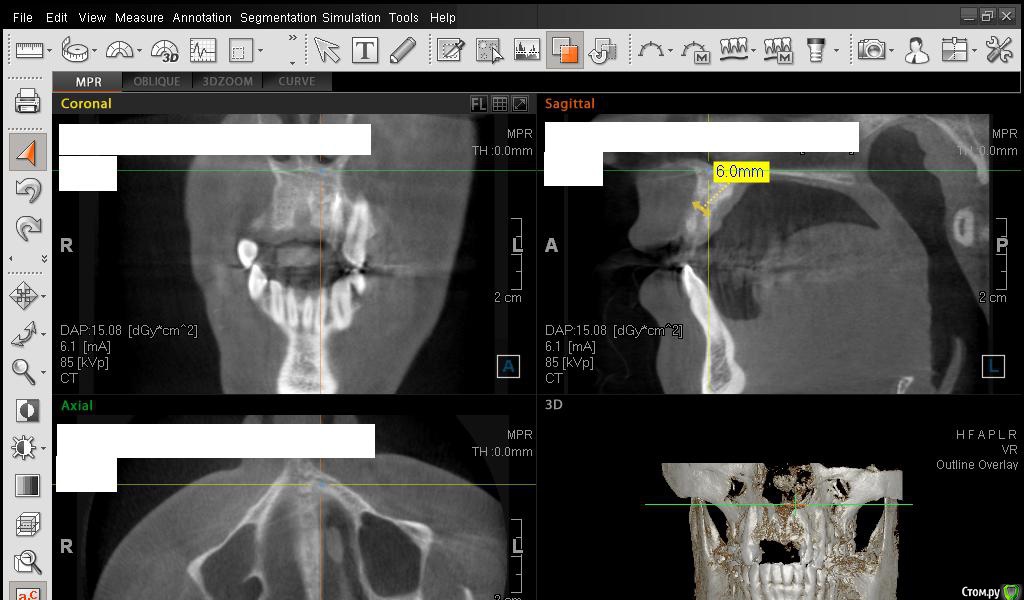

Сестричка Опубликовано 2 марта, 2015 Автор Поделиться Опубликовано 2 марта, 2015 Сделала замеры, надеюсь правильно? Старалась измерить наиболее уязвимые и тонкие места. Изначально планировались размеры имплантов 3 мм на 11 мм длиной. Смогут ли они туда встать? Ссылка на комментарий

Сестричка Опубликовано 2 марта, 2015 Автор Поделиться Опубликовано 2 марта, 2015 Кажется поняла, проекция креста неправильная была? навела на область десны Ссылка на комментарий

Сестричка Опубликовано 2 марта, 2015 Автор Поделиться Опубликовано 2 марта, 2015 Еще пара срезов Ссылка на комментарий

SDC Опубликовано 2 марта, 2015 Поделиться Опубликовано 2 марта, 2015 Интересны размеры беззубого альвеолярного отростка на самой вершине его или рядом с вершиной на расстоянии 1 мм. от нее в проекции будущего местоположения имплантатов.Желательно размеры проводить рядом с объектом (как в черчении)По-моему, диаметр 3 мм. подходит для имплантации без костной пластики, но без трансплантации десны, одномоментно с имплантацией, не обойтись. 1 Ссылка на комментарий